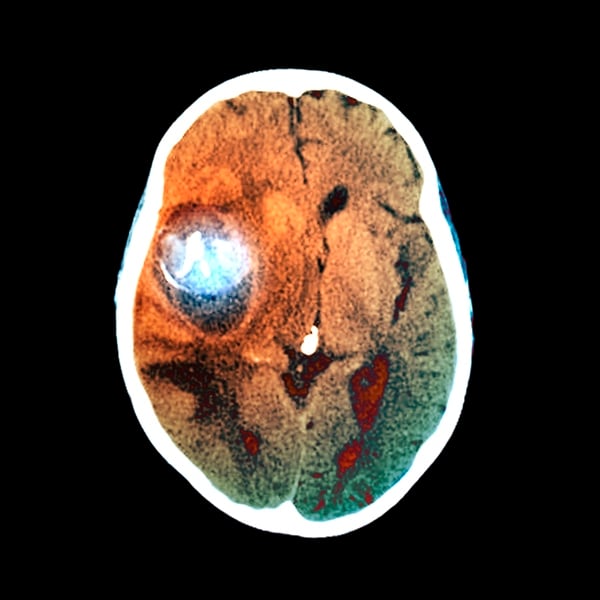

Aneurisma cerebral é uma dilatação em um dos vasos sanguíneos que levam sangue até ao cérebro. Ele tem o formato de um balão que pode aumentar de tamanho, se tornando cada vez mais frágil, até se romper. Quando isso acontece, um Acidente Vascular Cerebral (AVC) hemorrágico é provocado, podendo levar a pessoa à morte

SCIEPRO/ Getty Images

Existem dois tipos de aneurisma: o roto, que é o aneurisma que ainda não se rompeu, e o não roto, que está rompido e caracteriza uma emergência médica séria

ZEPHYR/SCIENCE PHOTO LIBRARY/ Getty Images

Exames de diagnóstico de imagem da cabeça, incluindo a tomografia computadorizada, a ressonância magnética ou a angiografia cerebral, são indicados para a avaliação das estruturas do cérebro